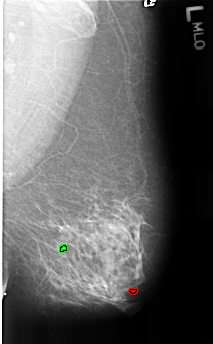

FILE: B_3182_1.LEFT_MLO.OVERLAY

TOTAL_ABNORMALITIES 2

ABNORMALITY 1

LESION_TYPE CALCIFICATION TYPE COARSE DISTRIBUTION N/A

ASSESSMENT 2

SUBTLETY 3

PATHOLOGY BENIGN_WITHOUT_CALLBACK

TOTAL_OUTLINES 1

BOUNDARY

ABNORMALITY 2